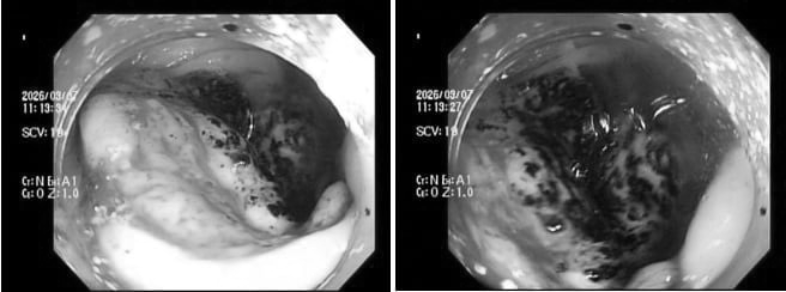

Tuy nhiên, kết quả xét nghiệm máu lại cho thấy tình trạng thiếu máu nghiêm trọng. Bác sĩ chỉ định nội soi đại trực tràng tiếp tục phát hiện một khối u dạng vòng nhẫn đang chảy máu âm ỉ. Kết luận giải phẫu bệnh khiến anh H. bàng hoàng với hai chữ ung thư.

Trường hợp chị P.V.P.U. (34 tuổi) cũng tương tự. Khi thấy vợ xanh xao bất thường, chồng chị đã đưa đi khám. Trước đó, bản thân chị chỉ thỉnh thoảng cảm thấy đau bụng nhẹ thoáng qua rồi hết nên nghĩ là rối loạn tiêu hóa thông thường, do stress. Tuy nhiên, kết quả thăm khám ban đầu lại cho thấy chị bị thiếu máu nặng. Ngay sau đó, bác sĩ chỉ định nội soi đại tràng và phát hiện một khối u lớn, bề mặt loét, rất dễ chảy máu. Kết quả mô bệnh học khiến cả hai vợ chồng sững sờ: Ung thư đại trực tràng.

Các khối u ở đại tràng, đặc biệt là đại tràng phải, thường không gây tắc ruột ngay mà có xu hướng loét và chảy máu rỉ rả. Lượng máu mất đi mỗi ngày rất nhỏ, không thể nhận biết bằng mắt thường vì lẫn trong phân. Tình trạng này kéo dài qua nhiều tháng khiến cơ thể dần cạn kiệt lượng sắt dự trữ, dẫn đến thiếu máu nặng. Đến khi cơ thể xuất hiện các triệu chứng rõ rệt, người bệnh đi khám, khối u thường đã phát triển lớn, thậm chí xâm lấn hoặc di căn.

Sàng lọc ung thư đại trực tràng có thể thực hiện nội soi. Đây là phương pháp hiệu quả giúp phát hiện sớm ung thư cũng như các tổn thương như polyp.